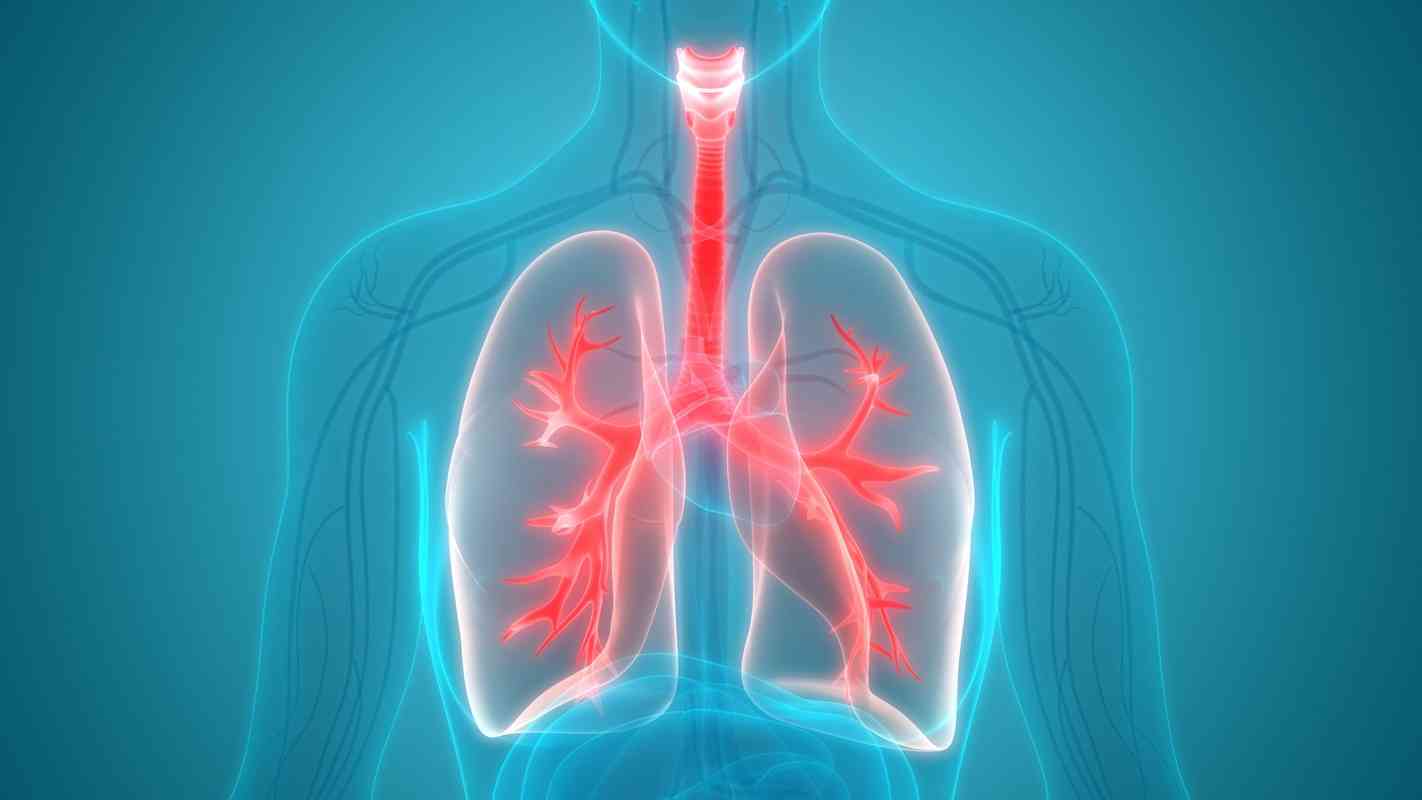

Την εποχή της πανδημίας του κορωνοίού, είναι ακόμα πιο σημαντικό να προσέχουμε την υγεία στους πνεύμονες μας. Ειδικά όσοι έχουν άσθμα, βρογχίτιδα και χρόνια αποφρακτική πνευμονοπάθεια, είναι σημαντικό να επιλέγουν τροφές που ωφελούν τα πνευμόνια.

Οι υγιείς πνεύμονες παίζουν έτσι κι αλλιώς σημαντικό ρόλο στην συνολικά καλύτερη λειτουργία του οργανισμού.